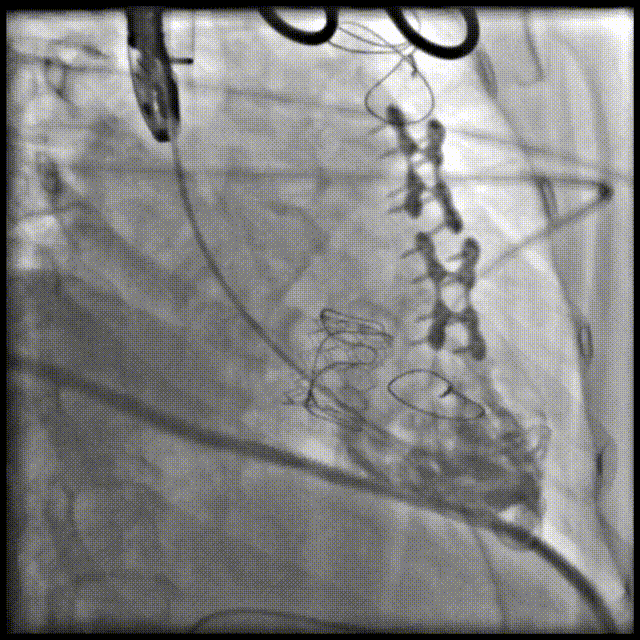

患者女性,62岁,既往三尖瓣位植入29# SAV猪瓣,超声提示三尖瓣人工瓣膜衰败,压差升高伴重度关闭不全。患者合并房颤伴长间歇、巨大右房、右心功能差,经独立专家委员会评判该患者属于外科手术高风险。术前经详尽影像学测量及多学科讨论,反复模拟分别经股静脉及经颈静脉入路输送瓣中瓣至三尖瓣的角度后,发现经右侧颈静脉入路瓣膜输送角度更理想。

手术顺利,经右颈静脉入路成功植入27号Renato球扩式瓣中瓣。瓣膜植入位置理想,无瓣周漏及中央返流。经查阅现有资料,经颈静脉路径成功完成三尖瓣“瓣中瓣”治疗在国内尚属首例。